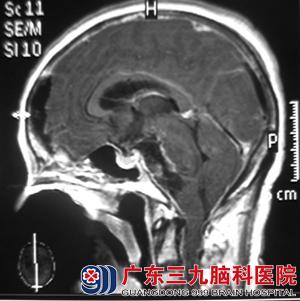

术后经过专业的治疗并配合康复训练,谢大姐的肢体基本恢复正常,行走自如。

术后